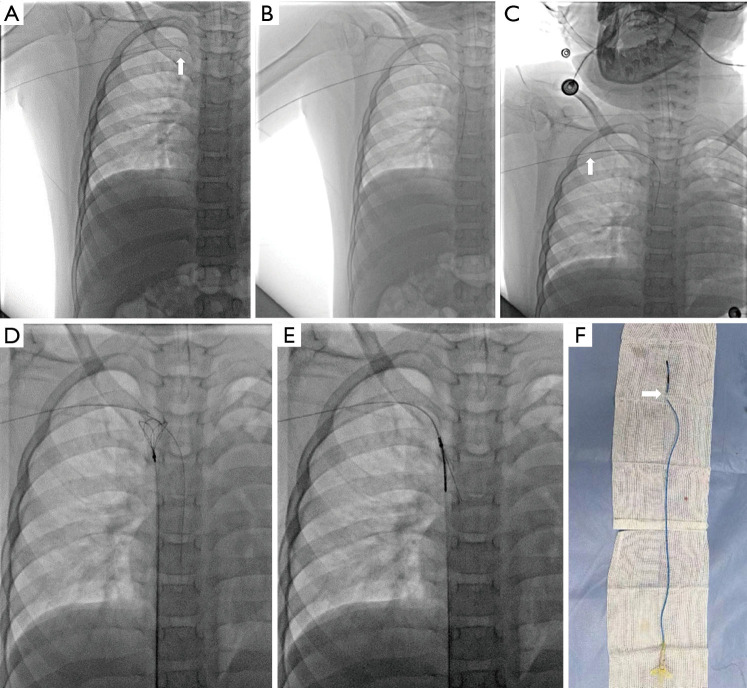

Case description: Three cases of difficult PICC removal were all children with acute lymphoblastic leukemia (ALL). All cases were male, range 3-6 years, mean 5.00±1.73 years, catheter indwelling time 289-433 days, mean 367.33±72.83 days. All three cases underwent PICC intubation via the basilic vein approach and all catheters were 3.0 French (Fr), silicone, single-lumen PICCs (Bard Access Systems, Inc., Salt Lake City, UT, USA). Removal of the PICC at the end of the treatment course was difficult. The pullback of the catheter went smoothly for the first few centimeters, but then resistance was encountered. The catheter did not move backward at that point, although we applied strong continuous traction. Several noninvasive approaches to remove the catheter (e.g., repositioning of the extremity, application of hot compress, and vascular massage) were all with no success. Eventually, the firmly adherent PICC was removed using fluoroscopy-guided guidewire-assisted technique in hybrid operating room safely and successfully.

Conclusions: Difficult PICC removal can result after prolonged dwell times. When conventional noninvasive interventions are unsuccessful, fluoroscopy-guided guidewire-assisted technique is a safe and effective method for the removal of adherent PICC.